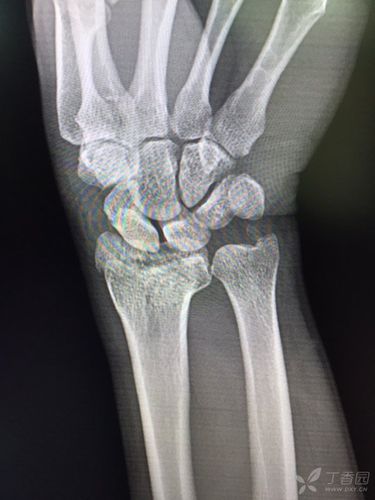

左手桡骨远端骨折图

左手桡骨远端骨折图,正常左手桡骨远端图片

桡骨远端骨折是否能手法复位成功?有没有手术指征? [病例帖]

左桡骨远端骨折

左侧桡骨远端骨折图片

桡骨远端骨折图片

左尺桡骨远端骨折图片